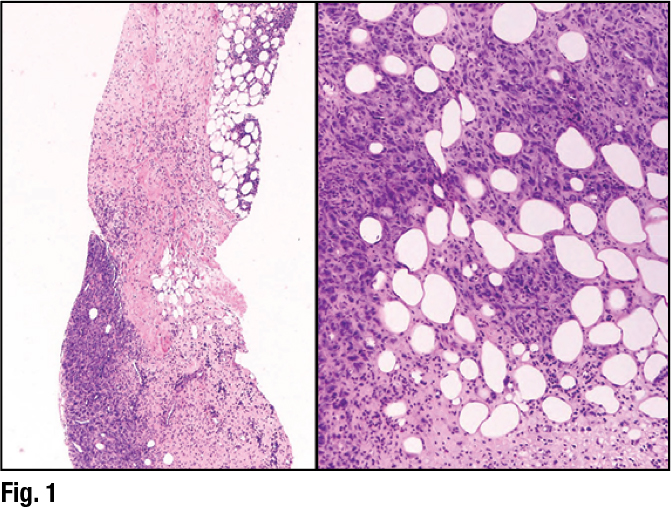

She showed an image of a lesion in a core needle biopsy that, in her view, looked like a grade two invasive ductal carcinoma (Fig. 6). “I think I would struggle to think this wasn’t a breast primary,” she said. The darker-appearing ducts in the left image are the normal terminal ductal lobular units. “The tumor cells are the larger nests of cells surrounding those ducts,” she said.

The ER stain was only weakly positive, however (Fig. 7), and she called this a point of caution. “If you have something that you think looks like a low- or intermediate-grade breast cancer, and the ER shows only weak positivity like this, you need to revisit your diagnosis because this should be strongly and diffusely ER positive.” In fact, the patient had a history of lung cancer and numerous lung nodules in addition to the breast mass.

Dr. Collins suggested that perhaps the best ancillary test is comparing the lesion in the breast to the prior tumor pathology, if available, and then performing supportive immunohistochemistry studies if needed. She presented images of the Napsin A and TTF-1 immunostains (Fig. 8). The final diagnosis: metastatic lung carcinoma.